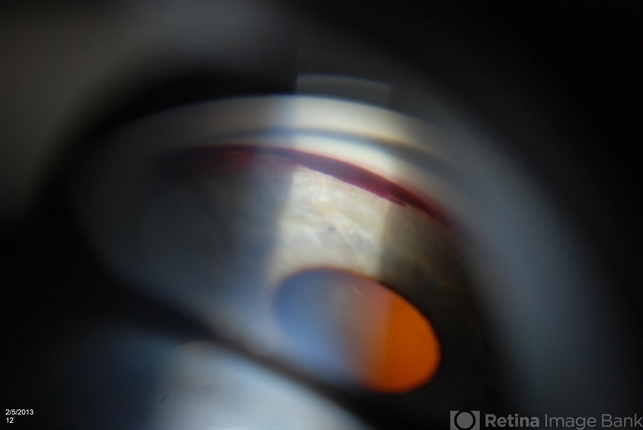

- gonioscopy, angle recession

- Jason S. Calhoun, Department of Ophthalmology, Mayo Clinic Jacksonville, Florida

- Photo slit lamp biomicroscope

- Patient with blunt trauma to the right eye due to a BB gun incident. Patient was present with a hyphema at 8-o'clock about 1mm thick. Gonioscopy photos were then taken to show blood from the hyphema entered into the anterior chamber. Patient had no angle recession in the right eye.